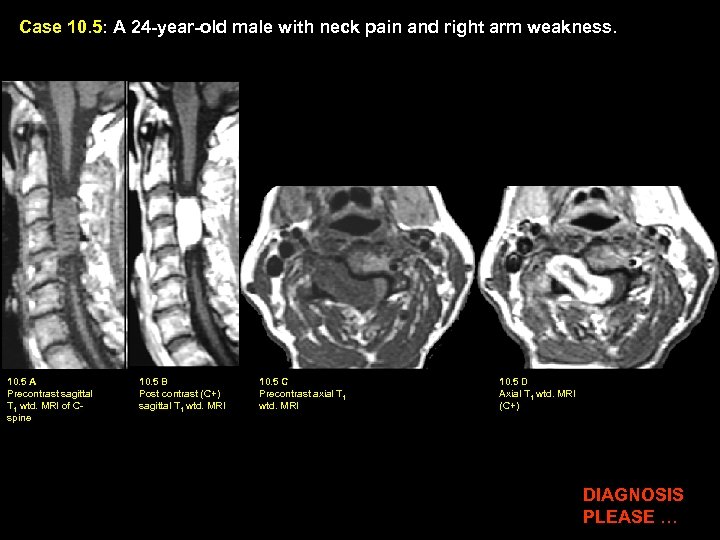

Case 10. 5: A 24 -year-old male with neck pain and right arm weakness. 10. 5 A Precontrast sagittal T 1 wtd. MRI of Cspine 10. 5 B Post contrast (C+) sagittal T 1 wtd. MRI 10. 5 C Precontrast axial T 1 wtd. MRI 10. 5 D Axial T 1 wtd. MRI (C+) DIAGNOSIS PLEASE …

Case 10. 5: A 24 -year-old male with neck pain and right arm weakness. 10. 5 A Precontrast sagittal T 1 wtd. MRI of C. spine 10. 5 B Post contrast (C+) sagittal T 1 wtd. MRI 10. 5 C Precontrast axial T 1 wtd. MRI 10. 5 D Axial T 1 wtd. MRI (C+) Findings: An enhancing intradural nerve sheath tumor (Schwannoma) is shown (red arrow in B and D). Dumbbell shape of tumor with intraspinal component (red arrow in D) producing cord compression (yellow arrow in D) and paraspinal tumor extension through an enlarged neural foramen (green arrow in C & D) following the exiting nerve root is best shown on axial post contrast image D. Diagnosis: Schwannoma arising from the spinal nerve root

Intraspinal Nerve Sheath Tumors Incidence: Most common intradural tumor • Solitary nerve sheath tumor is usually Schwannoma and commonly seen in adults. • Multiple nerve sheath tumors are usually neurofibromas and commonly seen in the pediatric age group with neurofibromatosis MRI Findings: • Dumbbell shaped enhancing intradural tumor with paraspinal extension through enlarged neural foramen is a characteristic feature of nerve sheath tumor. • Can cause cord compression. Treatment: Surgrey